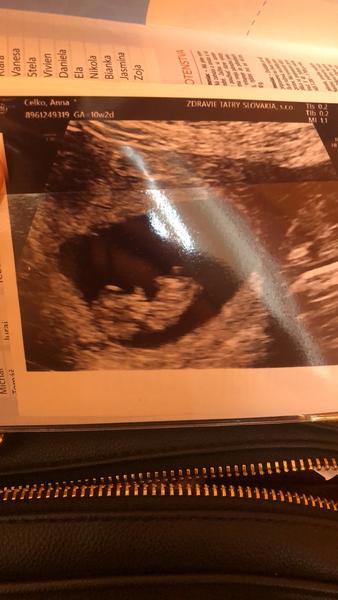

@viikkki Ahoj 🙂 Ja som uz bola na dvoch kontrolach. Naposledy vo stvrtok, som 10+2, aj babo je presne tak velke 🙂 7.12 idem na velky NT screening a sijove prejasnenie. To budem akurat koncit 12tt 🙂

@annaarkadjevna ahoj..skoro teda ako ja😍 ..ja som utorok bola 10+4 a tiez ma caka velky NT screening 1.12...🙏 a nemozem uverit ze to proste ide tak rychlo vsetko..za chvilu budu vianocr, prejde novy rok..a januar/februar uz bruskami sa budeme este viac a viac ako teraz kotulat..heh...